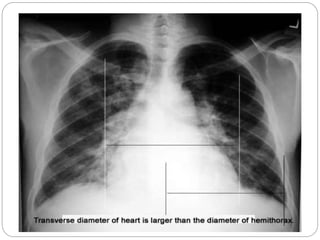

 Chest X-ray shows enlarged heart.

IMAGING STUDIES

 Chest roentgenography :

Cardiomegaly, pulmonary congestion, and

other findings consistent with heart failure

may be seen on chest radiography.